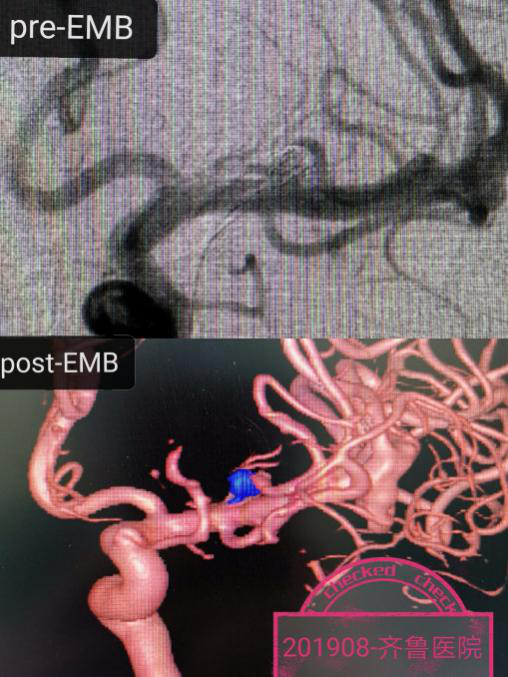

作为这样一例复杂的IV级神经介入手术,除了需要高超的手术技巧和团队的配合,更需要术中DSA提供清晰的路途、高质量的3D影像和支架弹簧圈等置入材料的准确显示。作为东软国产高端DSA设备的资深设计与应用专家,王东海教授凭借Neuangio 30C应用的丰富经验,带领邓林博士和王金磊医生在全麻下首先顺利填塞了大脑中复发动脉瘤(图-1),继而在路途下将两条支架导管应用交换技术顺利的送到目标血管,然后将两条4*20mm的Solitaire支架同步释放到位,继而在清晰的路途下将栓塞微导管准确送入动脉瘤囊腔,然后依次行微弹簧圈成篮、致密填塞,整个手术行云流水,一气呵成,术毕造影动脉瘤在支架的辅助下致密栓塞,载瘤动脉通畅(图-2)。病人麻醉清醒完全如同常人,齐鲁神经介入专家应用国产DSA设备再一次创造了生命的奇迹。

图-2:基底动脉尖宽颈动脉瘤双Solitaire支架辅助微弹簧圈栓塞术